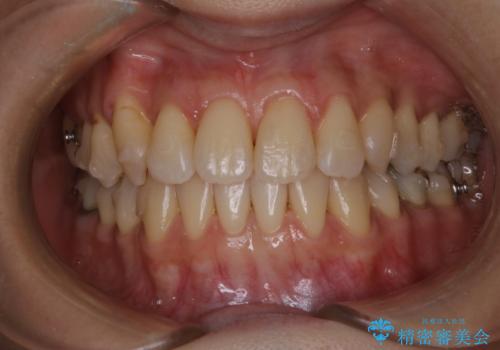

[ セラミック治療 ] 前歯を自然にしたい、セラミッククラウンのやりかえ

担当医 大元洋佑

![[ セラミック治療 ] 前歯を自然にしたい、セラミッククラウンのやりかえの症例 治療前](https://seimitsushinbi.jp/wp/wp-content/uploads/2022/02/771f39d281c5095ad94cbf96f730d007-500x350.jpg?v=1644041614)

![[ セラミック治療 ] 前歯を自然にしたい、セラミッククラウンのやりかえの症例 治療後](https://seimitsushinbi.jp/wp/wp-content/uploads/2022/02/b9ee13367ab56d7729121dc9c683836d-500x350.jpg?v=1644041633)